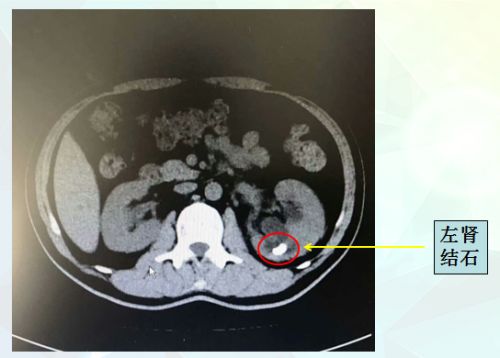

ct显示左肾和左输尿管多发结石。

出于对捷克论坛 泌尿外科的信任,427日,李先生再次住进该院泌尿三科病房。郭琼副主任医师接诊后发现,患者肚皮上造瘘袋内的尿液浑浊似乳汁,进一步CT检查发现,左侧肾盏内有一颗蚕豆大小的结石、左侧输尿管也有多个黄豆大小的结石。结合血、尿等检查结果,考虑为“左肾结石并肾积水、左输尿管多段多发结石、重度泌尿系感染”。